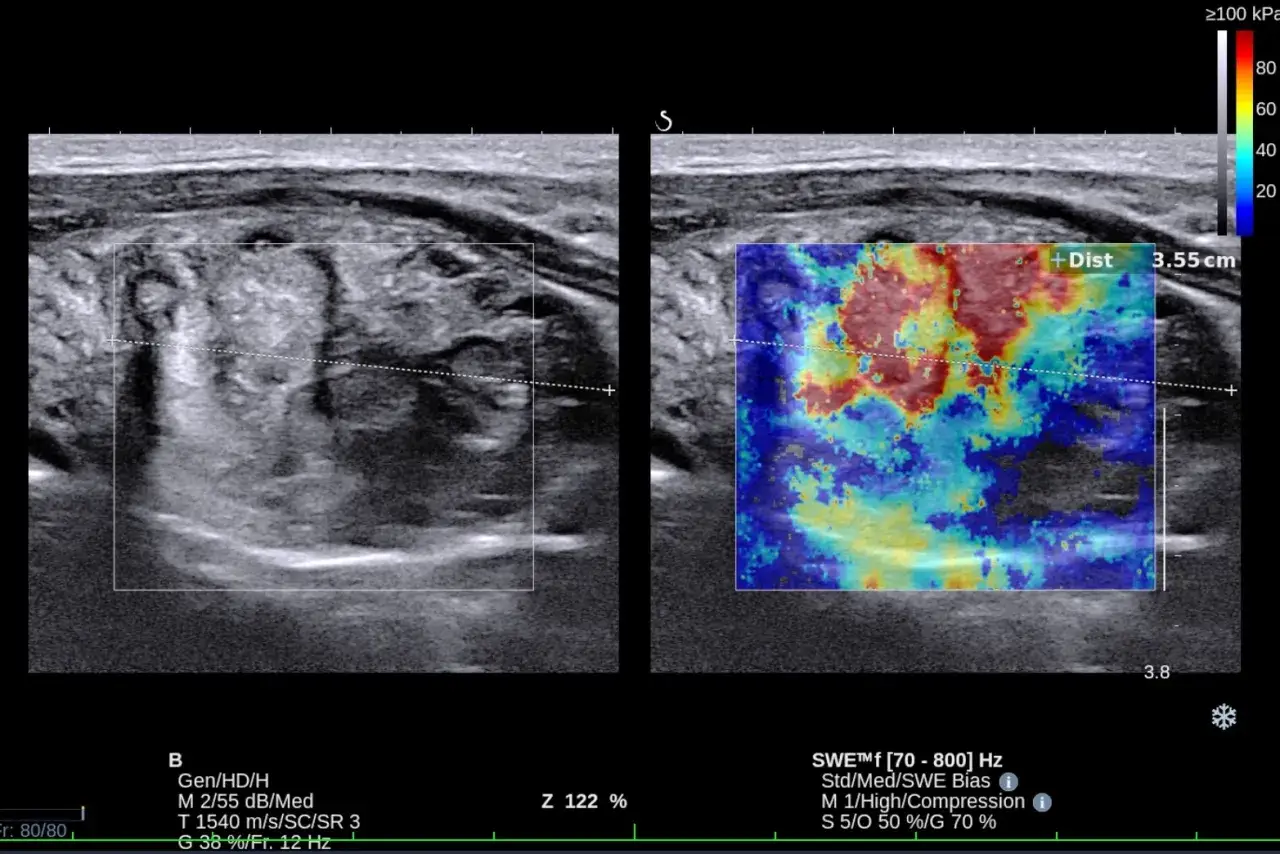

Nie da się ukryć, że zwiększona dostępność badań USG szyi w ostatnich latach znacząco przyczyniła się do wzrostu wykrywalności guzków tarczycy. Wiele z nich to tak zwane "incydentaloma", czyli zmiany wykryte przypadkowo podczas badania wykonywanego z innych przyczyn. Jednak to nie USG, choć kluczowe w lokalizacji i ocenie morfologicznej, jest decydujące w przypisaniu ostatecznego kodu. Kluczowym badaniem w różnicowaniu charakteru guzków jest biopsja aspiracyjna cienkoigłowa (BAC). To właśnie wynik BAC, oceniający komórki guzka, pozwala określić, czy jest on łagodny, złośliwy, czy też ma nieokreślony charakter. Bezpośrednio wpływa to na wybór właściwego kodu ICD-10 i dalsze postępowanie.